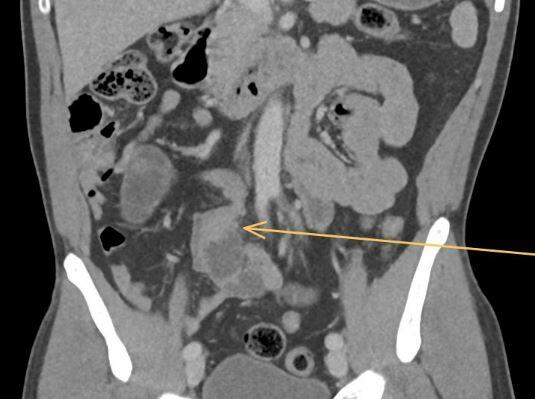

A 49-year-old patient was referred for emergency treatment via the REGA due to severe exacerbation of lower abdominal pain that had persisted for several days. Upon transfer, the patient was hemodynamically and respiratorily stable, and afebrile. On physical examination, diffuse tenderness was noted in the lower abdomen with a maximum tenderness located on the right side. Laboratory tests showed no abnormalities. The patient had no comorbidities and was not taking any regular medication. A CT scan of the abdomen with intravenous contrast revealed a calibre change in the small bowel with signs of venous congestion, raising suspicion of an internal hernia. No signs of free fluid or air were detected. Based on the clinical and radiological findings, we decided to proceed with diagnostic laparoscopy.

Intraoperatively, approximately 180 cm from the ileocecal valve, a 25 cm long segment of hyperaemic small bowel with the typical tapering pattern towards the mesenteric root, characteristic of MVT, was identified. Due to the absence of necrosis and active peristalsis in the affected segment, we refrained from performing a segmental resection or thrombectomy. A precise inspection of the entire small bowel revealed no internal hernia.